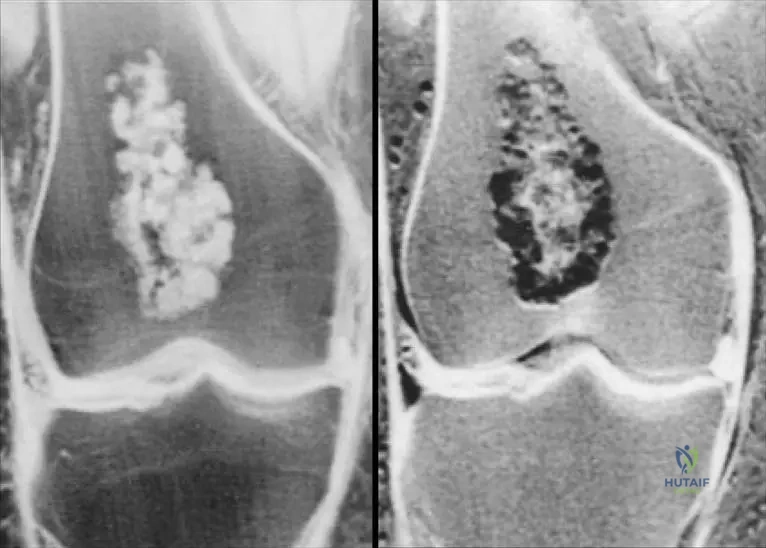

A 10-year-old child presents with multiple enchondromas and significant skeletal deformities.

View Answer & Explanation

Correct Answer: C

Rationale: The clinical context for Fig. 8.22 a, b explicitly links the images to "Ollier’s disease," which is characterized by multiple enchondromas and associated skeletal deformities.

Question 89

A 7-year-old patient is diagnosed with Ollier's disease.

Correct Answer: B

Rationale: The clinical context for Fig. 8.22 a, b states, "Short stature and osseous deformity secondary to Ollier’s disease."

Question 90

A 9-year-old child with multiple enchondromas is being evaluated for skeletal abnormalities.

A 10-year-old child presents with multiple enchondromas, leading to significant short stature and bowing deformities of the long bones. Radiographs demonstrate numerous intramedullary cartilaginous lesions throughout the appendicular skeleton. This clinical presentation is characteristic of which specific condition?

Rationale: The clinical context for Fig. 8.22 a, b explicitly states "Short stature and osseous deformity secondary to Ollier’s disease." Ollier's disease is characterized by multiple enchondromas, often leading to skeletal deformities and growth disturbances like short stature. Maffucci syndrome also involves multiple enchondromas but includes soft tissue hemangiomas, which are not mentioned. Multiple hereditary exostoses involve osteochondromas, not enchondromas. Fibrous dysplasia and Paget's disease are different bone disorders.

Question 98

A 12-year-old boy is diagnosed with Ollier's disease after presenting with progressive bowing of his left leg and a noticeable difference in leg length. Radiographs confirm multiple enchondromas. What are the characteristic skeletal manifestations associated with Ollier's disease, as depicted in the provided clinical images?

Rationale: The clinical context for Fig. 8.22 a, b explicitly states "Short stature and osseous deformity secondary to Ollier’s disease." This directly answers the question about the characteristic skeletal manifestations. The other options describe features not associated with Ollier's disease in the provided text.